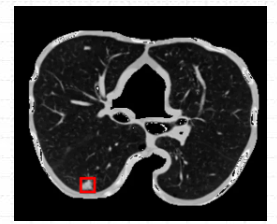

箭头指的地方可看见检测结果,可以说利用ModelArts平台训练出来的肺结节检测模型检测效果是很棒的。(直接看太小的话,可以点开图片放大看)

从最后实验的结果对比图来看,可以说利用ModelArts平台训练出来的肺结节检测模型检测效果是很棒的,虽然存在一定的肺结节病灶假阳性标记,但是这在小样本数据集的人工智能医疗检测中是会出现的情况。毕竟对于人工智能医疗检测模型来说,只用了300张标注图片就能达到这样的效果,真的让人感到惊喜。